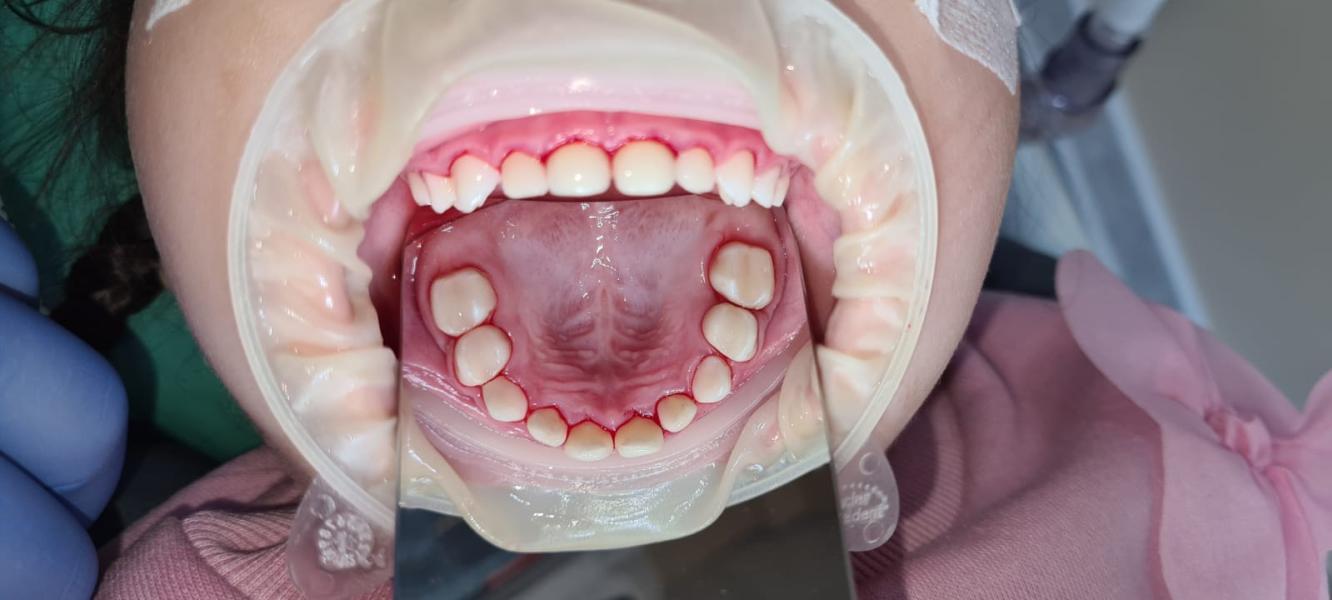

Наш врач Филиппов Григорий, астынныбыт аган от проделанной работы. Все вышло на 128тысяч, рассчитывали на 118. Ынырык астыктыктык онордо все зубы😍

Однозначно рекомендую

Еще поставили одну коронку